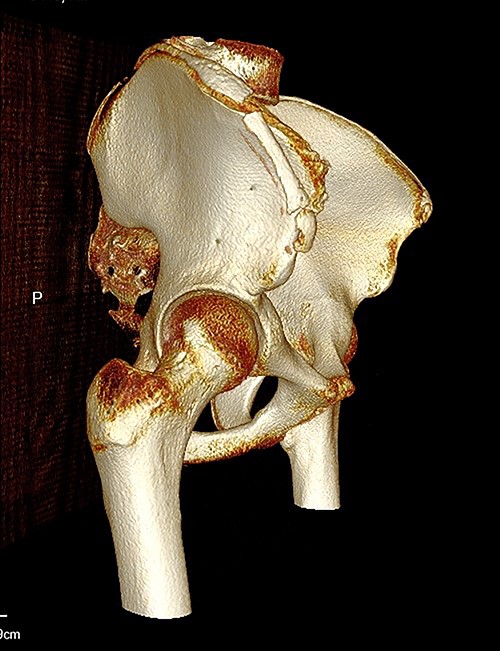

The anterior–posterior plain film X-Ray of pelvis demonstrated an avulsion fracture of the right ASIS and IC apophysis with 1.5 cm displacement (Fig. 1). Lateral view of the hip showed no extension into the joint. There was no radiological evidence of chronic overuse or previous injury. Computed tomography (CT) imaging was performed to better identify the injury; 3D volume reconstruction clearly demonstrated the unique fracture pattern of an ASIS avulsion in addition to an avulsion of the distal iliac apophysis extending ~5 cm with the described displacement (Figs 2–4).

3D reconstruction of tomographic CT scan illustrating avulsion fracture of ASIS and IC apophysis with its latero-inferior displacement (P - Posterior).